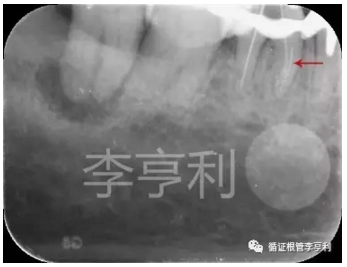

遠中角度投射,紅色箭頭為分離器械 (2017-05-16)

【輔助檢查】:遠中角度投射根尖片,見斷械影像移向近中,故判斷器械分離于近中頰根,根尖周未見明顯異常 (詳見CBCT┃如何使用傳統(tǒng)根尖片)

目前普遍建議使用術前CBCT來評估斷械情況,但由于本病例患者年齡較大,無法配合CT掃描時間,故采取成角度投照技術判斷器械的具體位置;